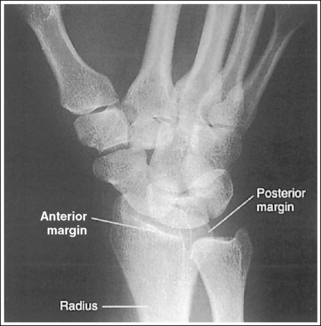

See Figure 4-36 and Box 4-13.

Contrast and density are adequate to demonstrate the pronator fat stripe and surrounding posterior wrist soft tissue.

• The pronator fat stripe is one of the soft tissue structures that should be demonstrated on all lateral wrist projections (Figure 4-37). It is located parallel to the anterior (volar) surface of the distal radius, is normally convex, and lies within 0.25 inch (0.6 cm) of the radial cortex. Bowing or obliteration of this fat stripe may be the only indication of a subtle radial fracture.

The wrist is in a lateral projection. The anterior aspect of the distal scaphoid and pisiform are aligned, and the radius and ulna are superimposed.

• A lateral projection of the wrist is accomplished by flexing the elbow 90 degrees and abducting the humerus until it is parallel with the IR, placing the entire arm on the same horizontal plane. Rotate the wrist into a lateral projection with its ulnar (medial) aspect against the IR (Figure 4-38). To ensure a true lateral projection, place the palmar aspect of your thumb and forefinger against the anterior and posterior aspects, respectively, of the patient's wrist joint, as shown in Figure 4-39. Adjust wrist rotation until your thumb and finger are aligned perpendicular to the IR.

• Detecting wrist rotation. The relationship between the pisiform and distal aspect of the scaphoid can best be used to discern whether a lateral wrist projection has been obtained. On a lateral projection, these two carpals should be superimposed, with their anterior aspects aligned. When the wrist is rotated, the anteroposterior relationship between the distal scaphoid and pisiform changes, and the pronator fat stripe is obscured. If the anterior aspect of the distal scaphoid is positioned posterior to the anterior aspect of the pisiform, the patient's wrist was externally rotated (see Image 45). If the anterior aspect of the distal scaphoid is positioned anterior to the anterior aspect of the pisiform, the patient's wrist was internally rotated (see Images 46 and 47). A second method of determining how to reposition a rotated lateral wrist projection uses the radius and ulna. The ulna is positioned anterior to the radius when the wrist was externally rotated and the ulna is positioned posterior to the radius when the wrist was internally rotated. Because the exact amount of superimposition of the radius and ulna depends on the position of the humerus, and their poor positioning is not as sensitive, you should always view the pisiform and distal scaphoid relationship when determining whether the wrist is in a lateral projection.